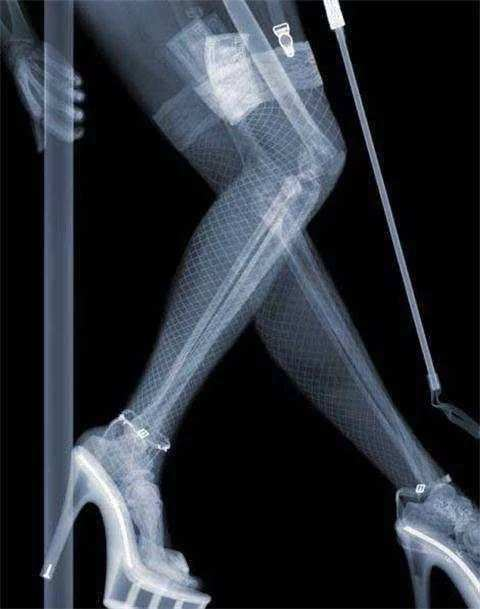

一些女性可能會認為,如果在通過安全檢查時被儀器看到,身為女性會很尷尬。經過調查后才清楚,安檢實際上分為兩種,第一種是檢查乘客的行李,第二種是檢查乘客身上是否有危險品。每個安全檢查儀器就像醫院的x光片。掃描后,它將被投射到電腦上。雖然它只是一個模糊的輪廓,但只要它是危險的,就可以立即被檢測出來,然后顏色就會被識別出來。其余的普通物品是灰色的。因此,女性同胞根本不用擔心這個問題。他們根本看不到個人隱私。在安檢過程中,安檢人員看起來就像在醫院拍攝一樣。男人和女人都是一樣的。他們看到的只是骨頭,不涉及隱私。